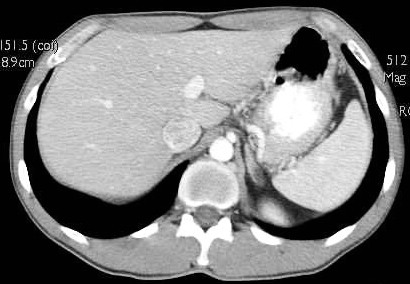

512 cm Mag R